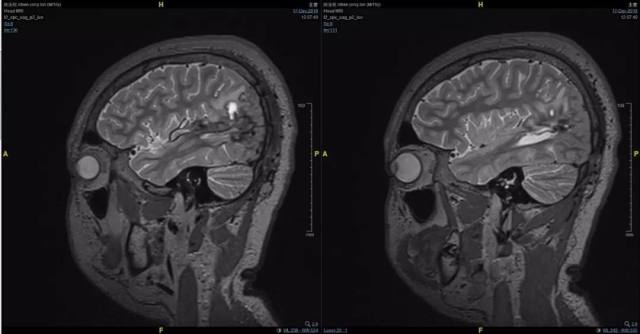

2、术前影像资料

图 3 术前 T2 矢状位:左颞顶枕血管畸形术后;混杂信号;考虑畸形残余伴出血。